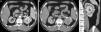

Antes del RS, no existía un consenso o una forma uniforme de cuantificar esta característica. El componente E designa puntos en una escala del 1 al 3: a los que se proyectan más del 50% de su extensión por fuera del contorno renal se les asigna un punto, a los que lo hacen menos del 50% se les da dos puntos, y si son completamente endofíticos (rodeados en 360° por parénquima renal no comprometido) reciben tres puntos (figs. 2–5).

Relación endofítico/exofítico: 1) la lesión predominantemente exofítica se proyecta más del 50% por fuera del contorno renal, por lo que se le asigna un punto, 2) la lesión predominantemente endofítica se proyecta menos del 50% por fuera del contorno renal, por lo que se le da dos puntos, y 3) la lesión completamente endofítica recibe tres puntos.

TCMC, en planos (a) axial (b) coronal y (c) sagital, de una mujer de 49 años con carcinoma de células claras de 5,5cm (flechas). La línea blanca delimita dónde debería estar el contorno renal para determinar el componente E (exofítico/endofítico). La masa se encuentra más del 50% exofítica, por lo que E es igual a un punto. Se pueden utilizar cualquiera de los planos. RS: 2+1+1+a+1=5a (baja complejidad quirúrgica).

TCMC, en planos (a) axial, (b) coronal, (c) axial en fase excretora y (d) sagital, de una mujer de 48 años de edad con carcinoma de células claras de 2cm (flechas). El tumor se encuentra menos del 50% exofítico, en relación con la línea blanca que delimita el contorno renal, por lo que E es igual a dos. RS: 1+2+3+x+3=9x (mediana complejidad quirúrgica).

TCMC, en planos (a) axial, (b) coronal, (c) axial en fase excretora y (d) sagital, de una mujer de 26 años de edad con carcinoma de células claras de 3cm con bordes calcificados (flechas). La masa es completamente endofítica, por lo que E es igual a tres. RS: 1+3+3+x+2=9x (mediana complejidad quirúrgica).

A pesar de que la mayoría de las masas son esféricas y simétricas, hay otras que no, por lo que la puntuación es dada según la característica predominante en cualquier plano (axial, coronal o sagital). A su vez, los contornos renales normales pueden estar distorsionados por la lesión, entonces se cuantifica tomando como referencia el sitio donde estaría el contorno renal si el tumor no existiera.

Para determinar el porcentaje exofítico del tumor se sugiere comparar las medidas de la superficie renal normal hasta el componente más exofítico con la medida de la superficie renal normal hasta el componente más endofítico. Estas dos medidas pueden ser tomadas en diferentes planos5.